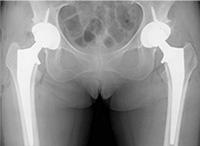

手术前X线图像

手术后X线图像

关节软骨磨损,关节的缝隙变窄,白色部分为人工关节。